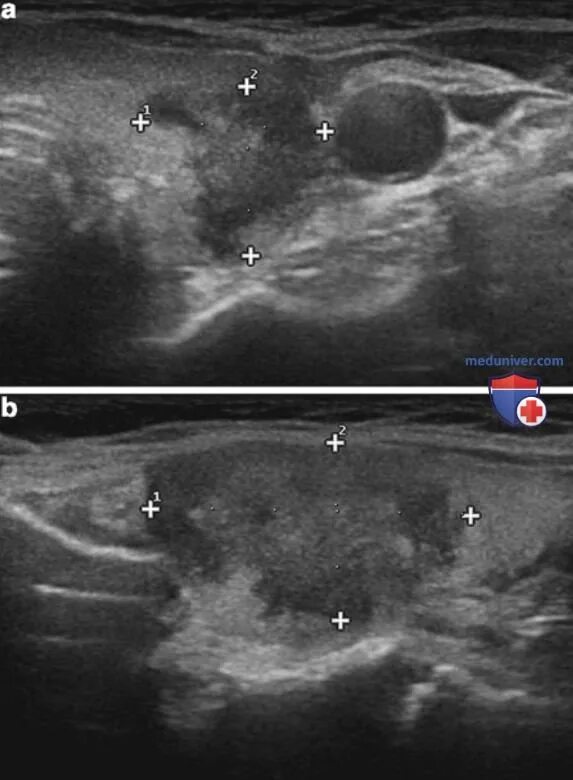

Диффузное увеличение железы